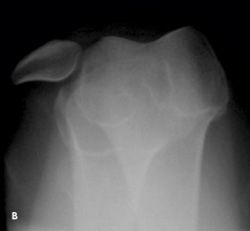

Knee pain following a soccer injury:The frontal radiograph revealsthat the patella is dislocated laterally(A). This is confirmed on the sunriseradiograph (B). A lateral radiographshows the malalignment of the patellawith the distal femur (C). Mostimportant, it also shows no fracture.Lateral dislocation of the patella isdiagnosed.